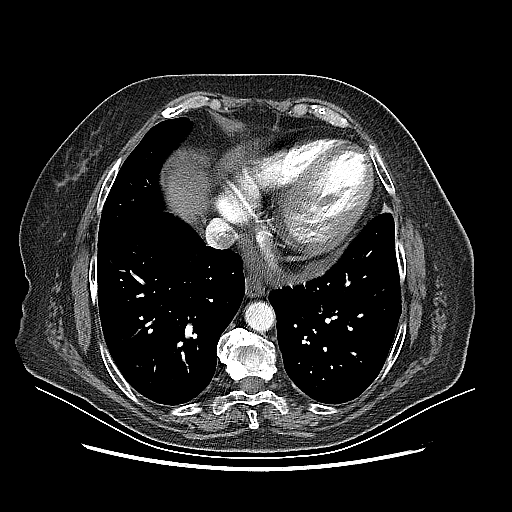

Generated VENOUS CT scan (A→B translation)

Full window (WL 1023.5, WW 4095 β†’ Low βˆ’1024, High +3071)

Mediastinum window (WL 40, WW 400 β†’ Low βˆ’160, High +240)